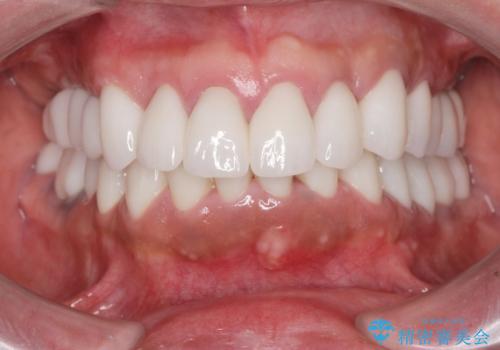

- 前医で行った前歯セラミック形態の改善、常に腫れぼったく歯ブラシの際に出血のある前歯部の治療を希望され来院されました。

前医により、前歯は歯ぐきの奥深くまで形成されこのままの状態でセラミックをやりかえたとしても歯ぐきの腫れの改善は難しい状況です。

歯周外科を行い歯と歯槽骨・歯肉の関係を是正することで歯ぐきの状態を改善し、将来に亘り安定した歯周環境の維持を期待できるセラミック治療を実践します。

歯ぐきが腫れたままの状態だと、違和感が生じるとともに常に炎症が存在する環境となってしまうので非常に好ましくない口腔内環境です。